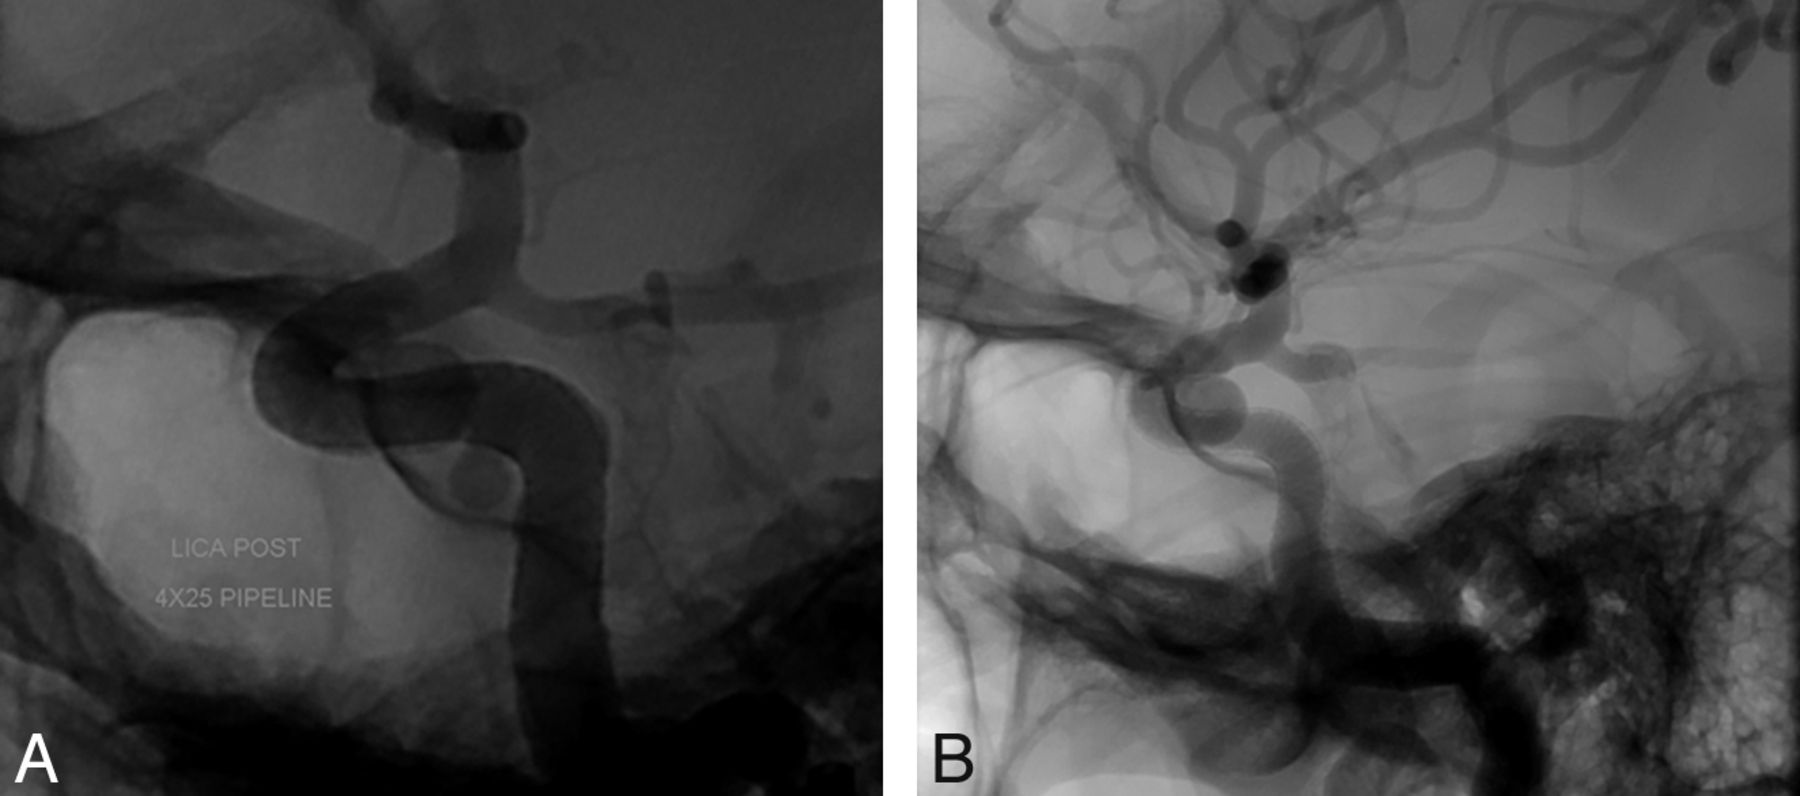

A 41-year-old woman presented to our institution for evaluation and treatment of 2 incidentally discovered aneurysms arising from the left superior hypophyseal segment and the left cavernous segment of the ICA. The aneurysm of the superior hypophyseal artery (SHA) measured 6.43 × 6.97 mm with a neck of 3.6 mm, and the cavernous aneurysm measured 2.97 × 3.63 mm with a 3-mm neck. The diameter of the petrous segment of the ICA was 4.1 mm, and the diameter of the paraclinoid segment was 2.7 mm. The decision was made to treat both aneurysms with a flow-diversion technique by use of the PED. The patient was prescribed aspirin and clopidogrel. With use of a triaxial system, a 4 × 25-mm PED was deployed across the aneurysms without difficulty, extending from the paraclinoid segment of the ICA to the petrous segment (Fig 3). Control angiography demonstrated adequate PED placement with contrast stasis in the SHA aneurysm. DynaCT was subsequently performed, demonstrating adequate stent apposition to the vessel wall with covering of the necks of both aneurysms. The procedure and postoperative course were uneventful, and the patient was discharged on the following day. Follow-up angiography 4 months later showed that the distal portion of the PED had migrated slightly proximally, with the neck of the SHA aneurysm no longer covered by the device. There was complete filling of the SHA aneurysm, with no contrast stasis. The cavernous aneurysm had completely resolved. The patient was scheduled for subsequent embolization.

A, A PED is deployed across 2 aneurysms extending from the petrous segment to the paraclinoid segment of the ICA. B, Follow-up angiography 4 months later showing that the distal portion of the PED had migrated slightly proximally, with the neck of the SHA aneurysm no longer covered by the device.